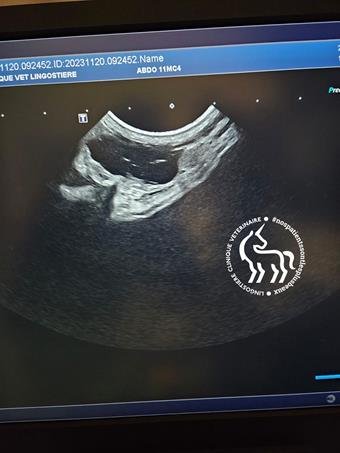

Lorsque le kyste est volumineux, une palpation abdominale réalisée par le vétérinaire peut orienter le diagnostic. Toutefois, l’échographie reste l’examen de choix pour confirmer la présence de kystes et évaluer leur taille.

Un bilan échographique peut détecter la présence de kystes ovariens.